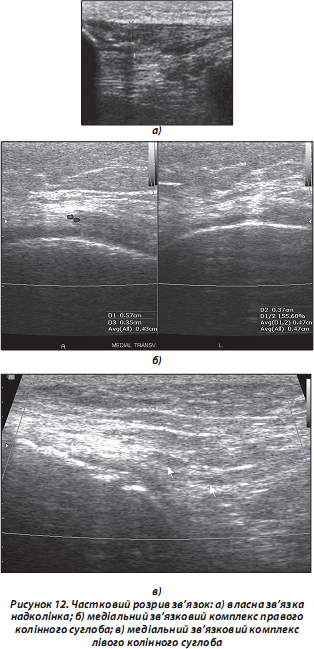

а) частковий чи повний розрив сухожилля — найчастіше виникає в місці прикріплення сухожилля до кістки чи м’яза (УЗД-ознака сухожиль з СО — часткове порушення фібрилярної структури сухожилля з формуванням анехогенного дефекту у вигляді синовіального випоту навколо ураженого сухожилля; УЗД-ознака сухожиль без СО — локальне потовщення сухожилля з порушенням контурів та фібрилярної структури останнього в місці дефекту; анехогенною ділянкою навколо ураженої зони за рахунок накопичення рідини в місці розриву). Розірвані кінці сухожиль, що не мають СО, скорочені, з повним порушенням їх фібрилярної структури, заповненням дефекту анехогенною рідиною (кров, жирова тканина чи СР) (рис. 12);